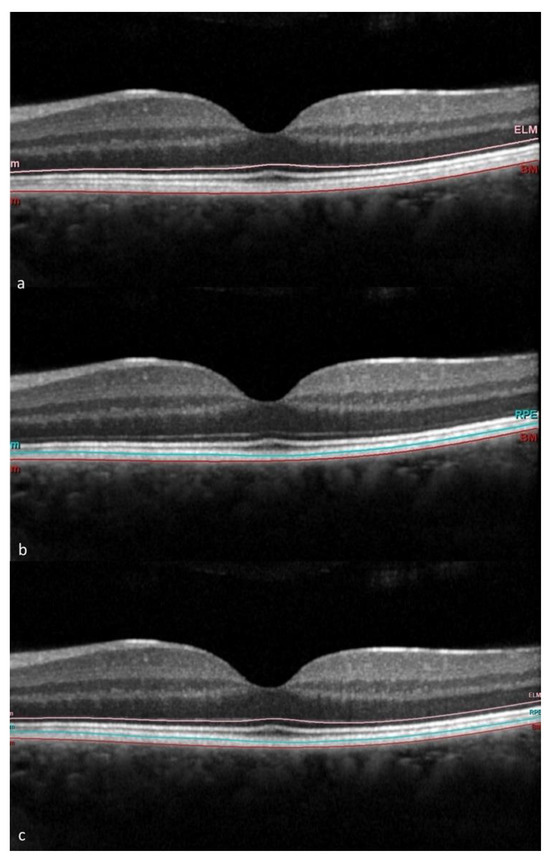

2.2. Imaging

3.2. OCT and OCTA Parameters